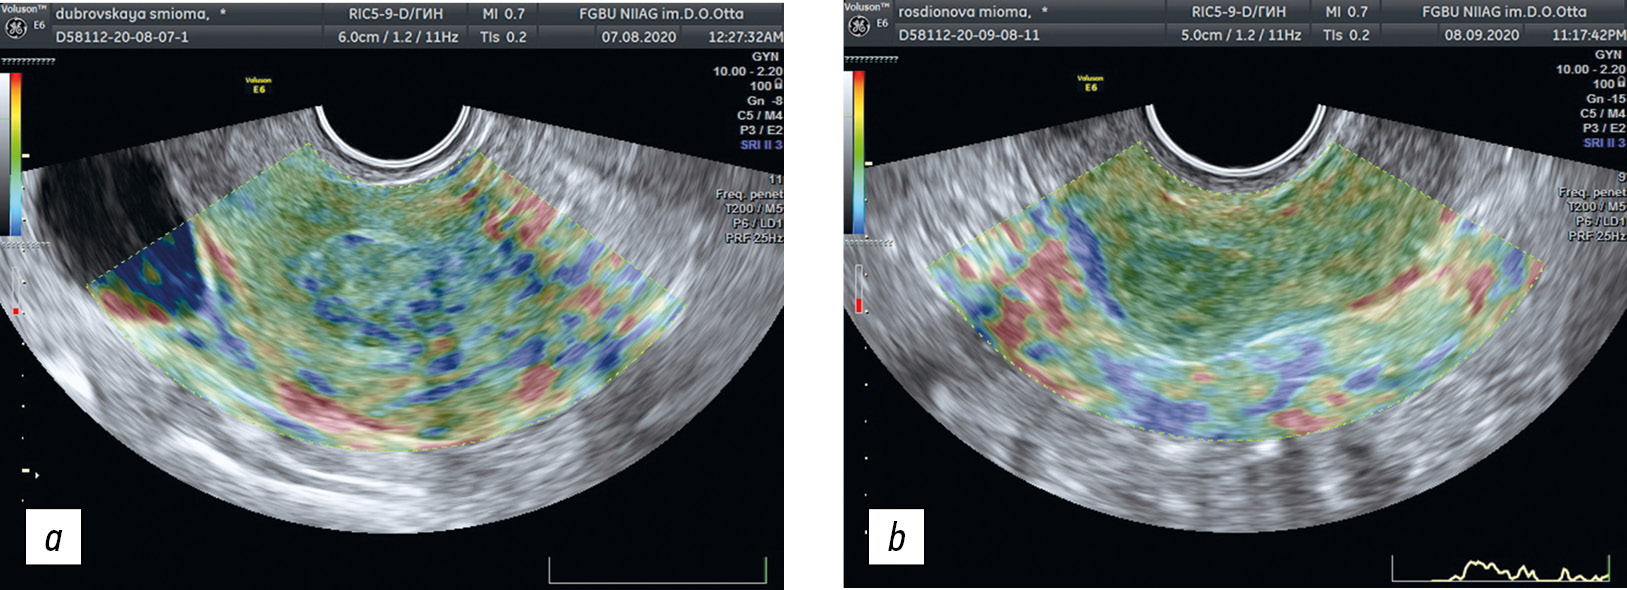

- Эластография (рис. 4). Компрессионная эластография выполнена после получения стандартного ультразвукового сагиттального среза матки при помощи приложения «Эластография», отображающего цветное кодирование участков миометрия с различной характеристикой упругости. Для визуальной оценки полученных эластограмм использовали классификацию В.Е. Гажоновой и соавт. [16] (рис. 2), коэффициент упругости (Strain Ratio, SR) вычисляли как результат отношения степени упругости тканей образования (узла, миомы) к соседним тканям миометрия, расположенных на той же глубине, что и образование, то есть одинаково реагирующих на компрессию.

Рис. 4. Эластограммы при: а — миоме матки (тип 2в); b — узле аденомиоза (тип 2б)

Fig. 4. Elastograms: а, for the uterine fibroids (type 2c); b, for the adenomyosis node (type 2b)